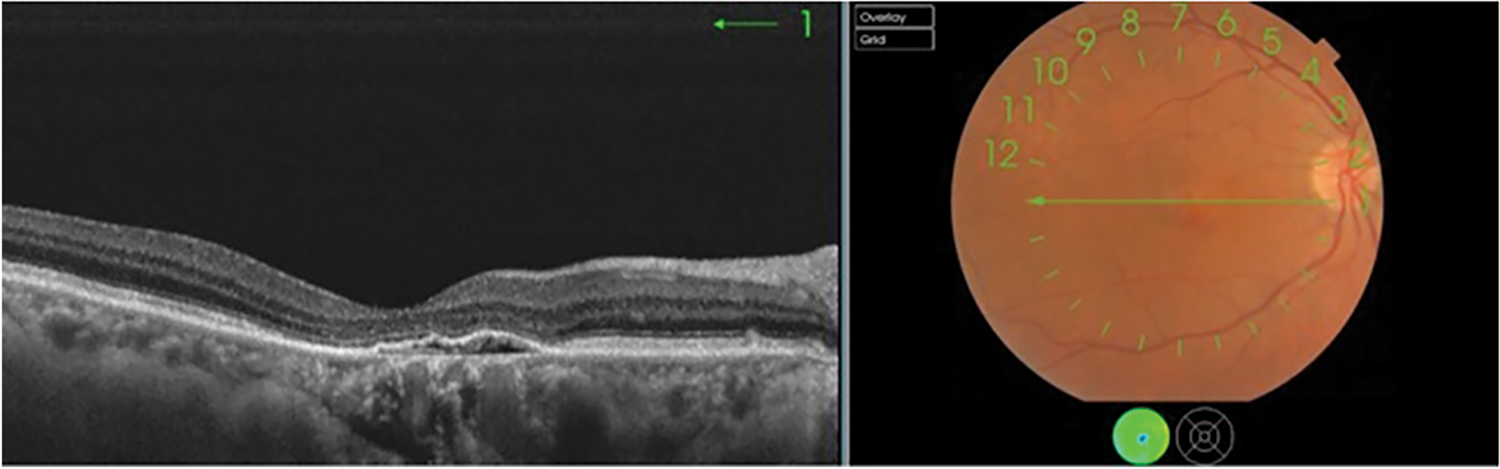

Macular neovascular membranes (MNV) are new impressions as shown in Fig. 1, damaging blood vessels that grow inside or beneath the retina, in an area called the choroid. When these vessels leak clear fluid or bleed inside or under the retina, causing vision loss. MNV is associated with many serious eye diseases, most commonly wet age-related macular degeneration. MNV MNV is also found in those with various conditions such as histoplasmosis, myopic macular degeneration, eye injury and many others.

Figure 1: Initial stage of choroidal neovascularization